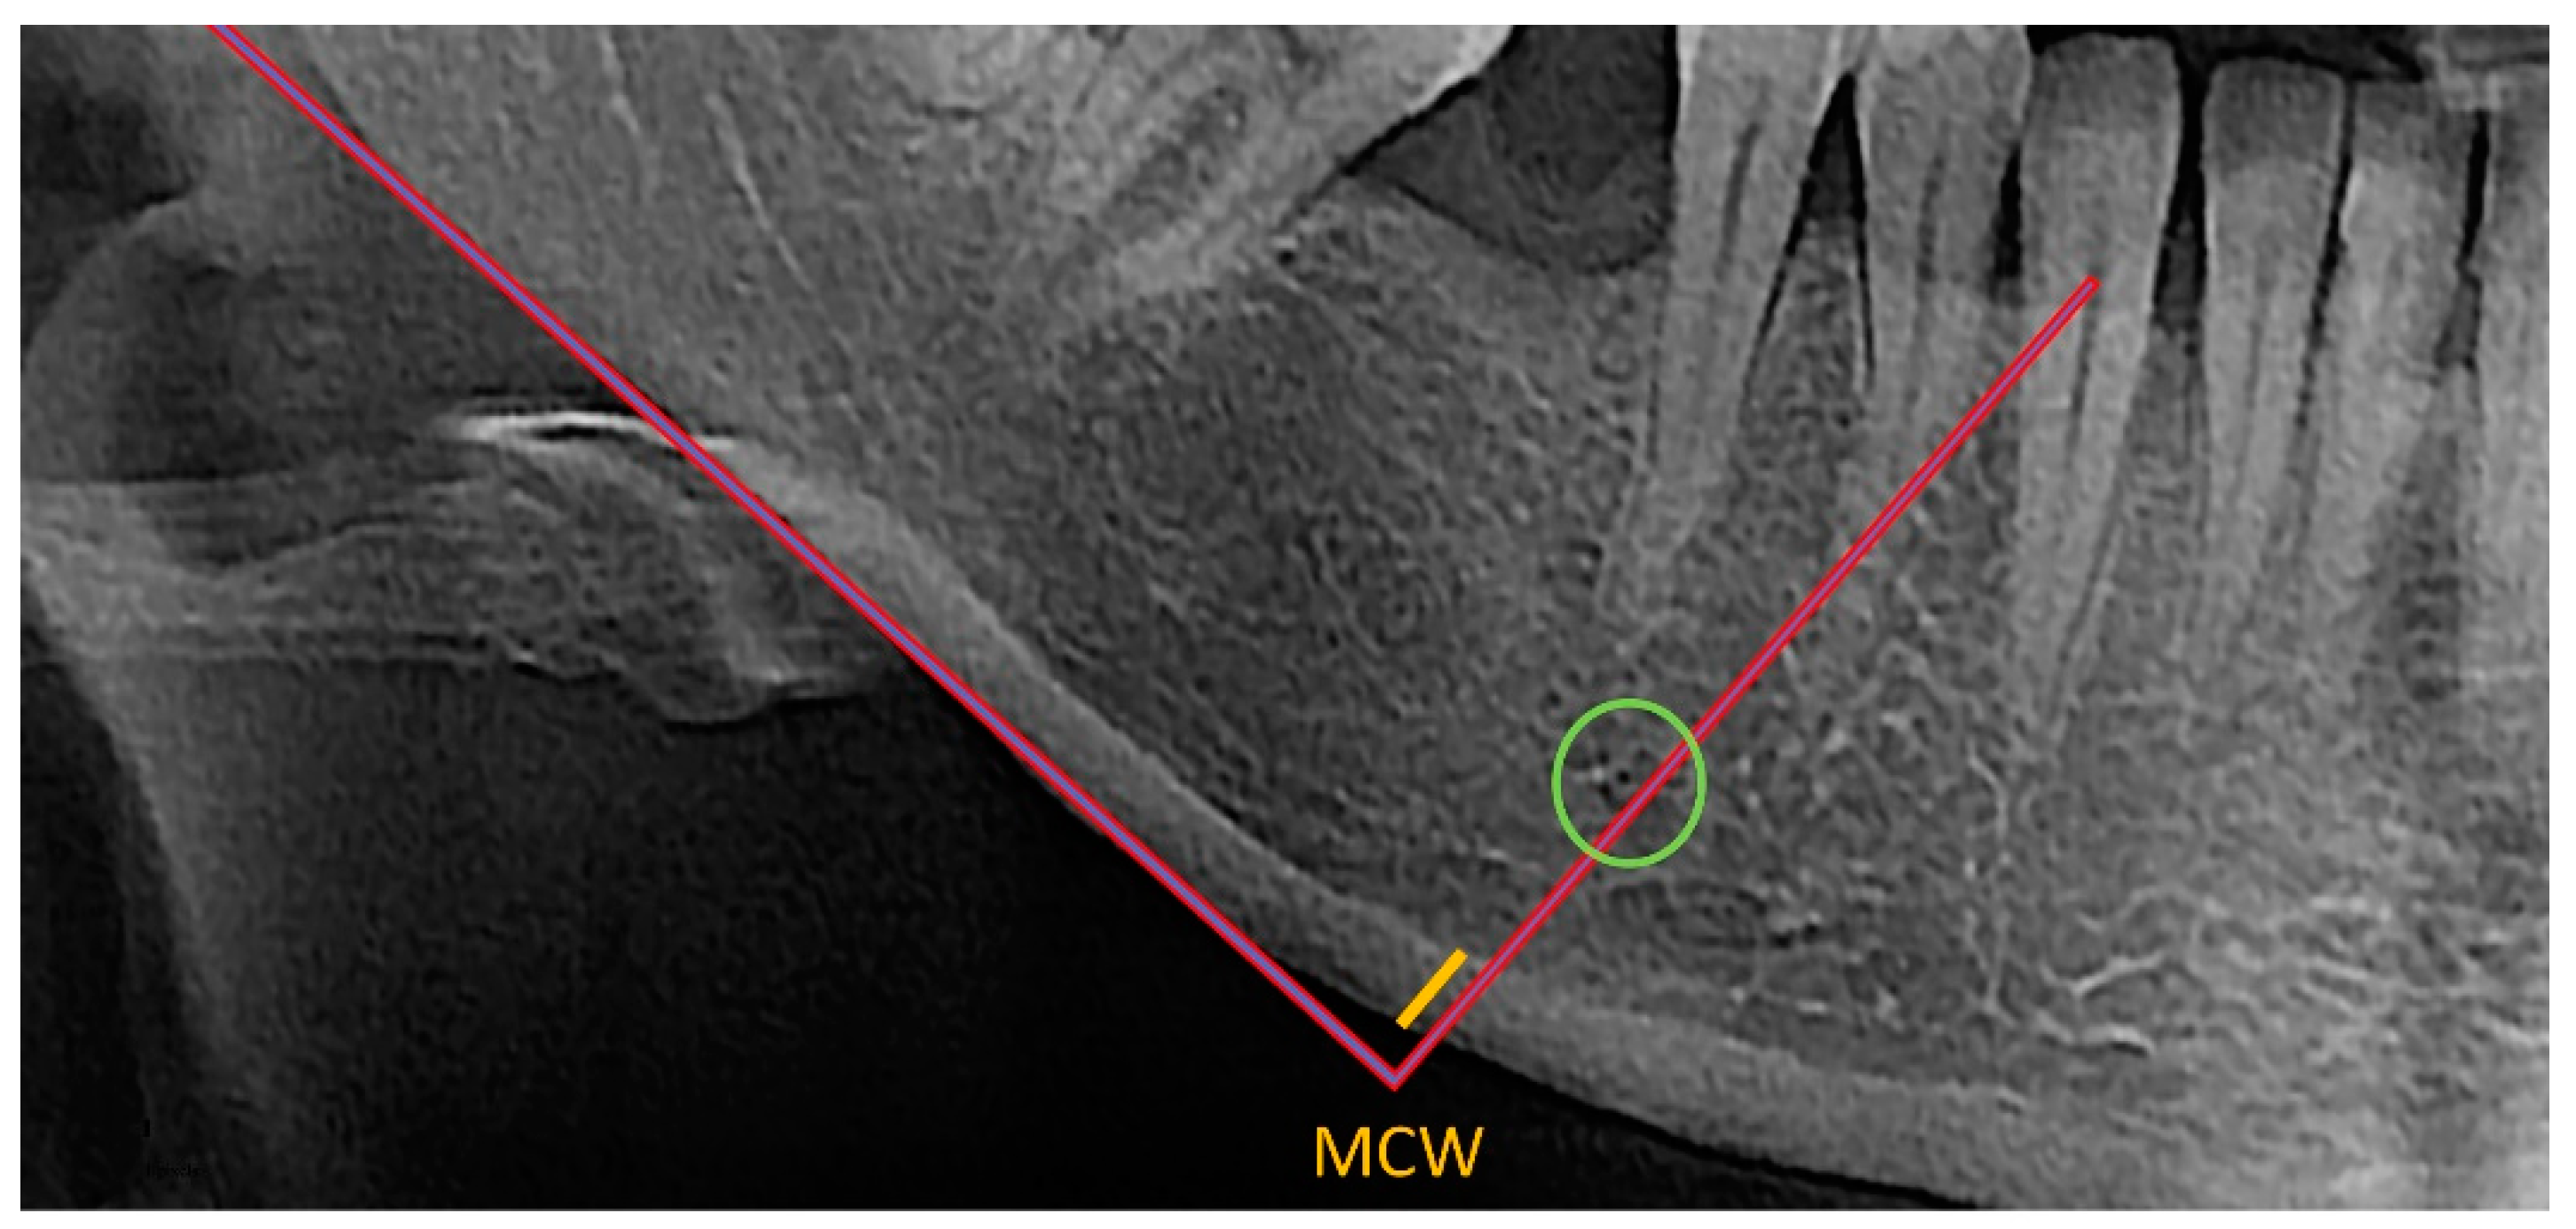

MCW was assessed by two independent observers who used the OSTEODENT project methodology on dental panoramic radiographs of both sides of the mandible. As shown in Figure 1, a line was traced from every foramen’s midpoint to the mandible’s lower border, which was then tangential to the lower border. Along this line, the thickness of the cortical bone at the lower border was evaluated [22,26,27]. All measurements were conducted using ImageJ software and recorded down to the closest 0.1 mm. Each patient’s bilateral measurements were averaged. The mean diameter of the metal ball was calculated using the measured width and height of the ball-bearing image [22].

Figure 1. Evaluation of the thickness (yellow line) of the cortical bone at the lower border of the mandible (MCW index) below and distally of the mental foramen (green circle).